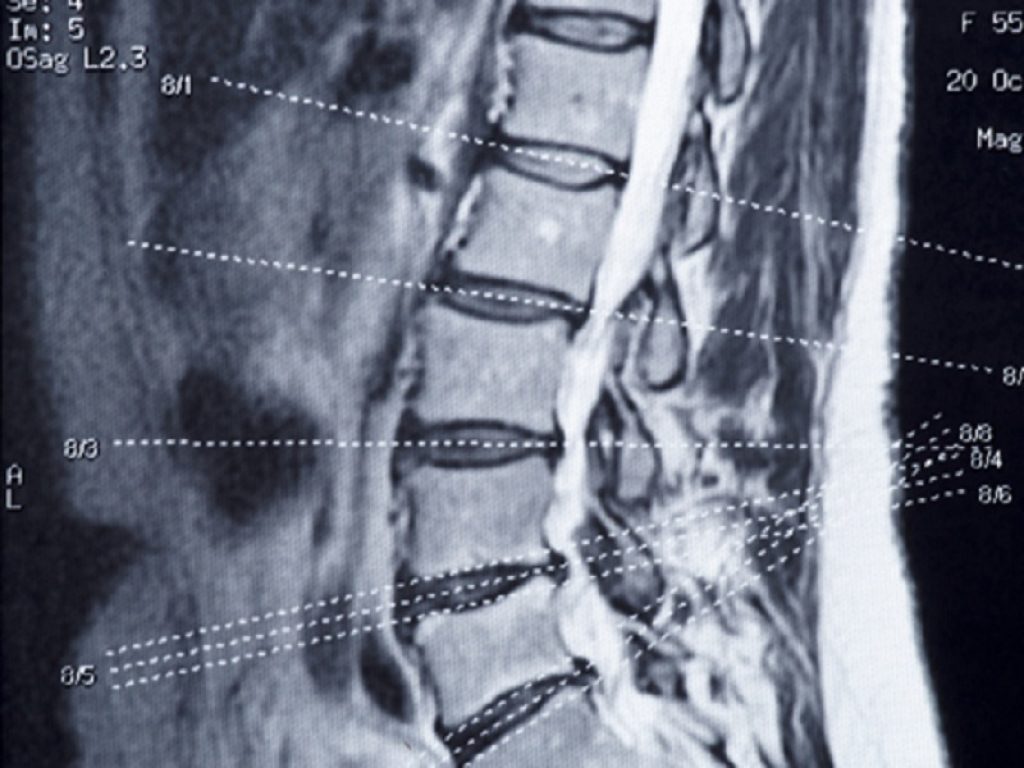

Frattura osteoporotica: troppi pazienti non ricevono adeguati trattamenti farmacologici di follow-up secondo un nuovo studio austriaco

Nonostante l’ampia disponibilità di trattamenti disponibili, ancora oggi la maggior parte dei pazienti che va incontro a frattura osteoporotica principale non riceve un adeguato trattamento farmacologico di follow-up. Questo l’allarme lanciato da uno studio austriaco di recente pubblicazione su Bone che sottolinea la necessità di colmare questo gap di salute non trascurabile, in ragione del progressivo invecchiamento della popolazione.